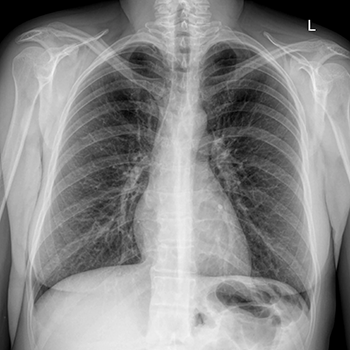

Знімок флюорографії легеньФлюорографія залишається одним із найбільш доступних методів перевірки стану дихальної системи, і багато користувачів електронних сигарет, особливо ті, хто обирає рідини на сольовому нікотині, цікавляться, чи здатна діагностика визначити факт паріння. На тлі популярності сучасних пристроїв питання про те, який вплив має вейпінг на флюорографію, набуває дедалі більшої актуальності. Попри те, що електронні сигарети вважаються менш шкідливими, ніж тютюнові вироби, вони все ж впливають на дихальні шляхи. Важливо розібратися, що саме може показати знімок легень, чи видно на ньому сліди пари, зміни структури тканин і чи відрізнить лікар вейпера від курця. Нижче розглянемо міфи й факти, спираючись на актуальні дані досліджень, а також відповімо, чи можна курити перед флюорографією і чи вплине це на результати.

Розмови про те, що флюорографія нібито здатна «видати» вейпера, трапляються досить часто. Однак важливо розуміти, що метод спочатку призначений для виявлення патологій легень, а не звичок. Він не показує нікотин, хімічні речовини чи склад пари. Єдине, що відображається на знімку, — стан легеневої тканини: наявність затемнень, інфільтратів, ознак запалення або структурних змін (фіброз, ділянки за типом «матового скла», патологічні порожнини з рідиною або без). Позначок про те, що людина використовує вейп, у висновку лікаря-рентгенолога не з’явиться.

Однак опосередковано вплив електронних сигарет на легені може бути помітним. Часте паріння здатне подразнювати слизову, викликати хронічне запалення, провокувати сухий кашель або бронхіт. Але навіть у такому разі визначити джерело подразнення (електронні чи звичайні сигарети, часті ГРВІ, алергія) за одним знімком неможливо. Саме тому питання, чи покаже флюорографія, що людина курить вейп, майже завжди має негативну відповідь, особливо за відсутності ускладнень.

Що бачить лікар на рентгені легень вейпера і курця

Під час аналізу знімка досвідчений лікар-рентгенолог звертає увагу на структуру легеневої тканини, стан бронхіального дерева, чіткість та інтенсивність судинного рисунка, а також наявність затемнень, ущільнень або інших патологічних ознак.

У більшості вейперів рентген не показує виражених хронічних змін, особливо якщо стаж паріння невеликий, а пристрої та рідини якісні. У легенях можуть спостерігатися лише поодинокі ознаки подразнення слизової або легкої гіперреактивності бронхів, що не формує серйозної патологічної картини.

У курців сигарет ситуація інша. Тютюновий дим містить продукти горіння, смоли та токсичні сполуки, які роками впливають на легеневу тканину, спричиняючи характерну рентгенологічну картину.

Флюорографія і куріння: відмінності знімків курця сигарет і вейпа

Рентген легень після вейпінгу — вплив електронних сигаретТема «Флюорографія і куріння» значно краще вивчена щодо звичайних сигарет. У курця зі стажем рентгенолог може побачити:

• потовщення стінок бронхів;

• посилення і деформацію легеневого рисунка;

• ознаки хронічного запалення, пов’язані з бронхітом;

• розширення повітряних просторів, характерне для ранньої емфіземи;

• локальні затемнення в легенях при пневмонії;

• ділянки дрібних структурних змін і елементи фіброзу.

Подібний вплив електронних сигарет на легені відсутній. Вони не спричиняють накопичення важких продуктів горіння та смол, через які страждають курці. Але при тривалому й інтенсивному використанні пристроїв, неправильній техніці затяжок, частому перегріві спіралі або виборі неякісних рідин зі шкідливими домішками,

Чи може флюорографія показати сліди вейпінгу: висновки

Важливо розуміти, що флюорографія показує лише наслідки куріння, а не сам факт використання пристрою. Завдяки дослідженню можна побачити виключно наявні зміни (запалення, затемнення, фіброз, ділянки «матового скла»), але неможливо визначити, чи використовує людина звичайні сигарети, багаторазові або одноразові POD-системи, МОДи або кальян.

Чи покаже флюорографія, що людина курить вейп? За нормального стану легень жодних «слідів вейпінгу» лікар не побачить. А за наявності запалення буде видно лише сам факт патології, але не її причину.